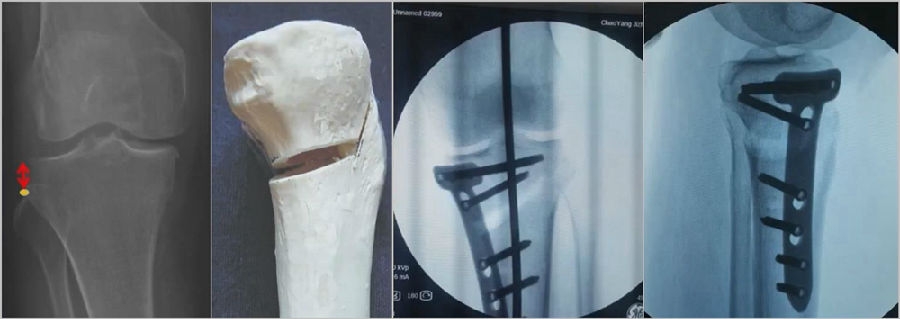

(2)Ⅱ型骨折

当出现Ⅱ型骨折时要特别注意,因为此时截骨的远端就是骨折的远端,近端只有上胫腓周围骨筋膜存在,所以相对来说Ⅱ型骨折并不稳定。

首先用拉力螺钉复位,调整好力线。然后做结构性植骨,延迟负重,所谓延迟负重就是延迟到外侧合页和上行截骨线处达到初始愈合,然后再让患者进行负重。如果不做结构植骨加延迟负重,就会出现一些非常严重的现象,如不愈合。

拉力钉复位,结构性植骨

左侧患者未植骨正常负重,术后4个月不愈合;右侧患者非结构性植骨过早负重,术后1年未愈合